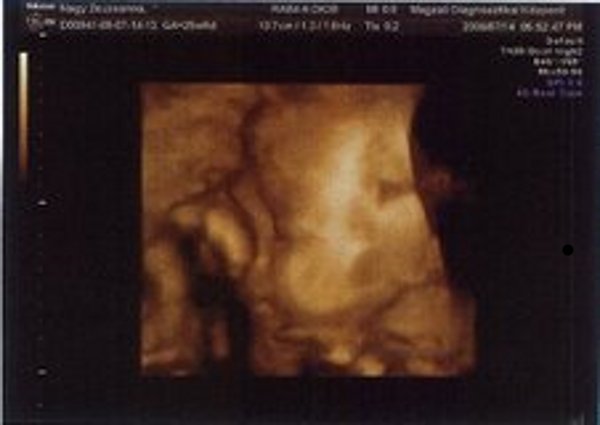

Nézzétek a kukim:

Kép

Zsuzska

Milyen édes kis arcocskája van :)

Édes kis turcsi orra lesz, mint apukájának van.... anyum szerint tiszta apja :lol: :lol: :lol: :lol: :lol: :lol: :lol: :lol:

Benőkéd már most jelentős mérettel rendelkezik, mi lesz később? :lol:

Amúgy nagyon édibogyó! :D

Jajj de szép Benőke! :) És tényleg látszik a kis kukija. :) Jajj meg azok a csöpp kis lábacskák! :) Na és a kis pofija... :) Megvallom könny szökik a szemembe... Hogy mennyire várom már, hogy láthassam a teljes valójában! :) GOndolom te még jobban.:)

Leírhatatlan érzés volt látni ilyen formában is. Anyum szerint már most tiszta apja a gyerek :lol: :lol: :lol: :lol: :lol: :lol: :lol: :lol:

Hát igen, apja méreteire hajaz a drágám úgy látszik :shock: :shock: :shock: :shock: :shock: :shock: